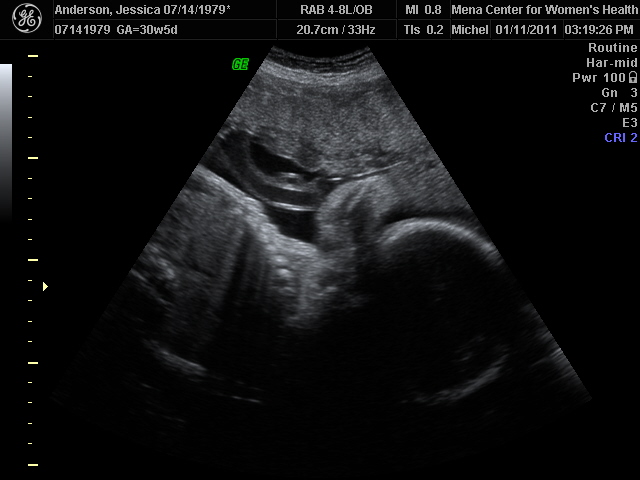

Hollis in 4d!!

I'll just start by saying he did NOT cooperate in any form or fashion. We did not get a single face shot. In fact the only 4d we got was of his butt! HA! We do know with 100% accuracy his is in fact a boy! It appears he has a TON of hair! It was floating all around in the scan. Our tech said its a lot and it is long. Also, he is a chunk! At 30 weeks he weighs FIVE lbs! The average weight is around 3 lbs. She asked how big our last one was and I told her10.5 she said this one is well on his way to that. She was very apologetic about the lack of face pics, she said Hollister gets the award for worst baby ever. Sounds about right:)! I am a bit disappointed about not seeing his sweet little face, but am looking that much more forward to the surprise in March. Until then I can stare at the pic of his sweet little bottom:)!

pics of our mystery man!